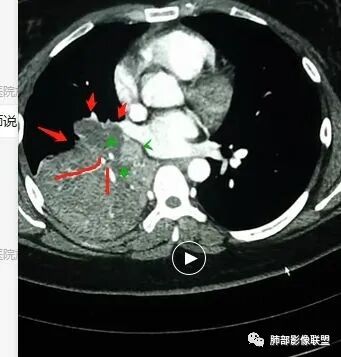

我再捋一捋支气管

右主支气管

上叶支气管

中间段

争议的地方这是上叶?中叶?

说实话图不全

关键点——中间段支气管堵塞处

没有显示

都是以肺内的病变为主

其实关键点在中间段支气管

断层面是没办法的情况,因为图太多,需要选择

各人看片的习惯不同,选的图像也不一样

通过视频显示中间段堵了

支气管腔内占位

远端低强化,提示粘液很多

纵隔淋巴结大

本病例特点是中叶病灶和下叶病灶不一样,支气管腔内的病灶又是怎么样的呢?我们要是有沿支气管重建的冠状位、矢状位会更有利于分析。第一,中叶病灶明显粘液样改变、低密度,且低密度区有占位效应、膨隆,确实要考虑粘液表皮样癌。第二,中叶和下叶支气管显示不出来,但血管显示出来了。中叶病灶血管稀疏、细小,下叶病灶血管粗大、走形正常。朝外肺不张实变,不是单纯的肺不张,肺不张一般体积明显缩小、血管聚拢,该病例肿瘤于其中成分不一样,所以上叶部分病灶考虑为下叶病灶占位效应及膈面向上推压引起,中叶萎缩。综合腔内堵塞、纵隔淋巴结肿大要考虑恶性。

支气管层面位置朝下强化明显,支气管腔内、远端是有差异的,腔内哪些是粘液?哪些是肺组织?是单纯实变?还是合并感染?还是外围都是病变?支气管腔内病变?

该病灶明显实变,需鉴别是内朝外,还是外朝内病变。该病灶内血管走形自然,肺门区血管无明显受压移位,且非起源于胸膜,不张肺组织或者不张肺组织夹杂炎性病变。而非典型肺炎型肺癌及外朝内的其他恶性病变。

内朝外病变是支气管腔内病变?还是支气管周围病变呢?如果支气管周围大恶性肿块灶,那其内血管也不应走形自然,应杂乱无章,所以只能是腔内病变引发支气管周围病变。